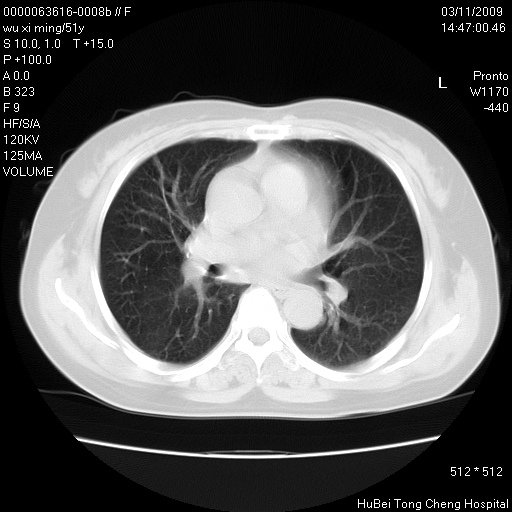

患者 女,51岁。因“胆囊炎,胆囊结石”,行常规术前胸部x线检查发现:右上肺结节病灶,建议行进一步检查。患者无咳嗽、咳痰及咯血等呼吸道症状,近期出现背部疼痛不适。

胸部ct轴位平扫(层厚10mm,螺距1.5,重建间隔10mm;部分层面:层厚3mm,螺距1.0,重建间隔3mm),图像如下:

右肺周围型肺癌伴肺内转移信胸椎转移

1、周围型肺癌。(毛刺正、血管束集征,分叶。)

集束征,胸膜牽拉征,毛刺,淺分葉高度提示ca.

右肺周围型肺癌伴肺内转移及胸椎转移。已无手术机会。